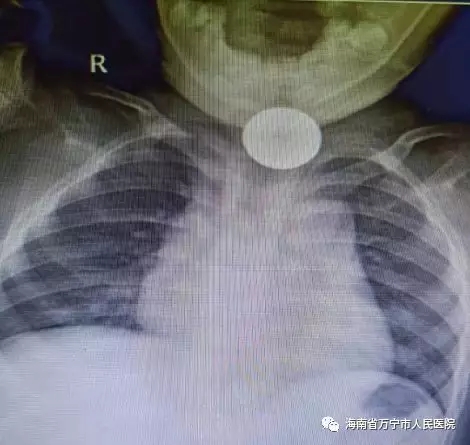

我院门诊的接诊医生根据患者的情况,立即收入耳鼻咽喉科住院。耳鼻咽喉科的曾祥发医生根据患者的情况,立即做胸部X线等相关检查,发现一枚直径约25mm的硬币卡在了孩子的食管入口处。由于孩子还小,无法自行排出,但这枚硬币若不及时取出,可能造成孩子食道梗阻、穿孔、破裂等情况,如果硬币松动堵住气管,会引起窒息危及到孩子生命。在这种危险的情况下,耳鼻咽喉科熊卫红主任说我们要通过食管镜检查来取出异物。

患者的胸部X线(圆形白色阴影部分为硬币)